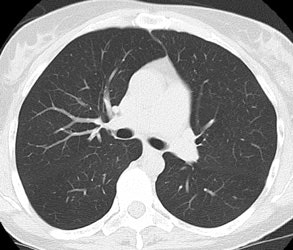

Screening versus diagnostic CT imaging: The left image is from a low dose lung screen CT scan. The right image is from a diagnostic chest CT. Although the screening exam is slightly more noisy and not good for evaluation of soft tissue structures, the exam is of more than adequate diagnostic quality for evaluation of the lung parenchyma. |